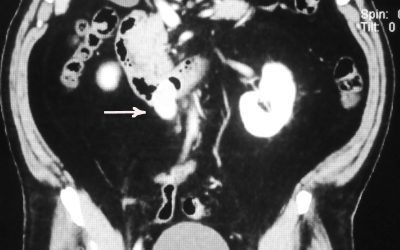

GIST duodenali: soluzioni chirurgiche e analisi di un caso clinico

di Enrico Ganz Nel seguente articolo sono esaminate le possibilità chirurgiche per l’asportazione di un GIST duodenale. La decisione di trattare questo tema è successiva alla mia constatazione che alcuni chirurghi hanno una certa ritrosia verso le soluzioni...